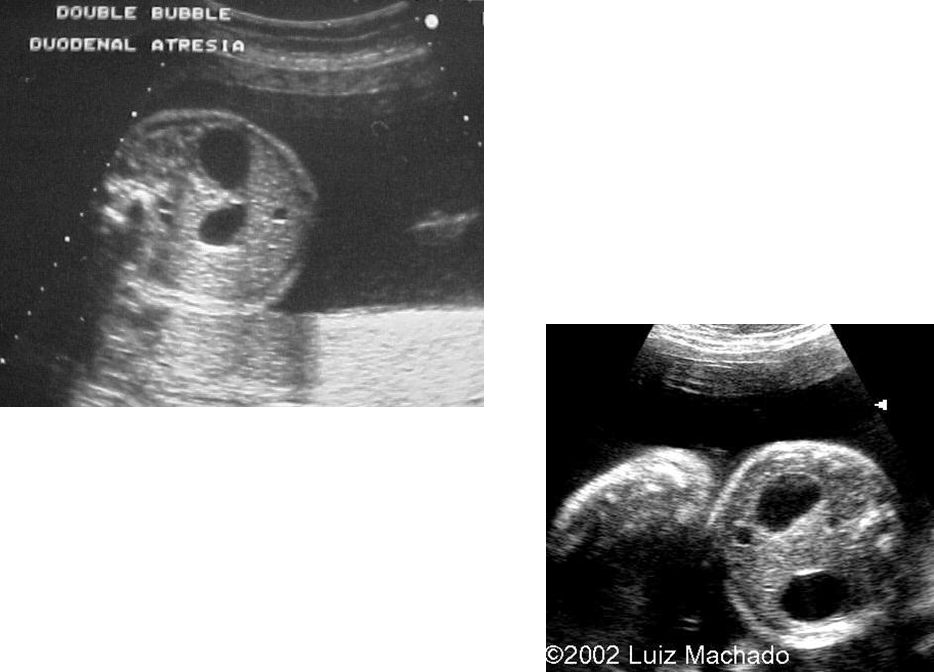

What are these images showing?

Duodenal Atresia

What is this image showing?

What is Duodenal Atresia?

Double Bubble Sign

What are the US findings of duodenal atresia?

2 anechoic structures in upper abdomen, look for communication